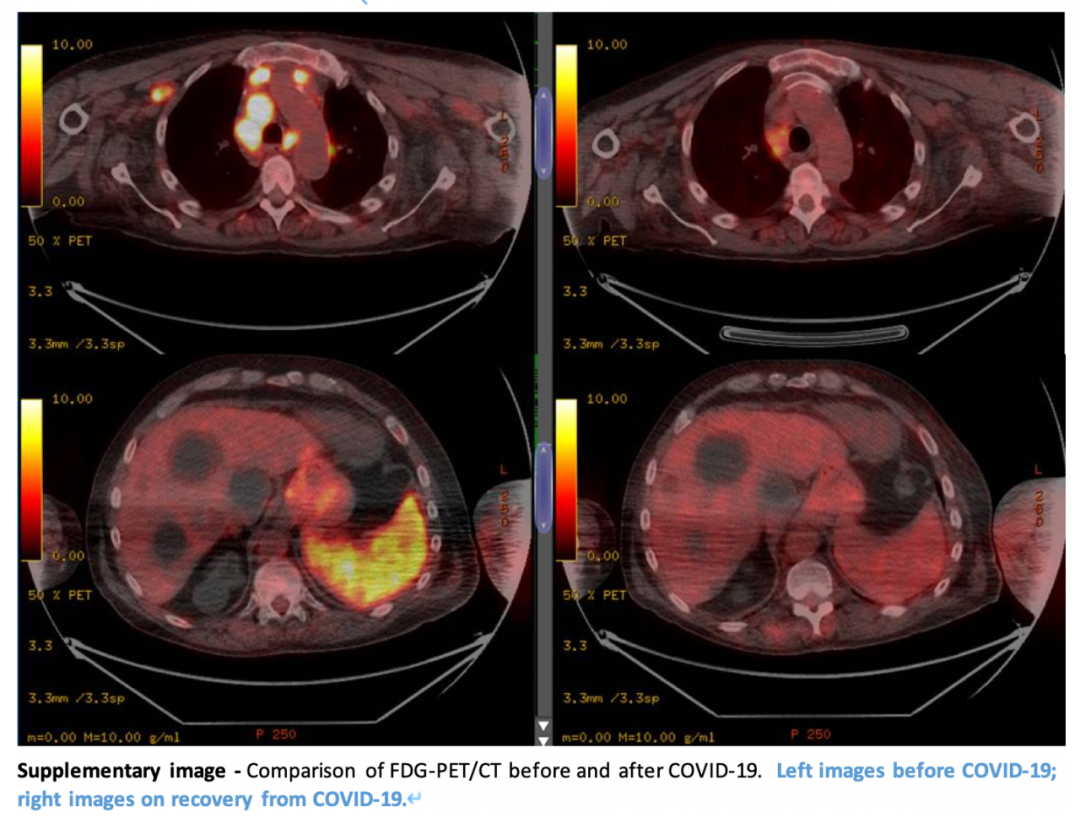

CT检查照片显示:可触及的淋巴结病变减少,淋巴结病变广泛消退,整个区域的代谢摄取减少。

前后对比不要太明显!

左图为最初的PET/CT扫描结果

右图为4个月后的PET/CT扫描结果